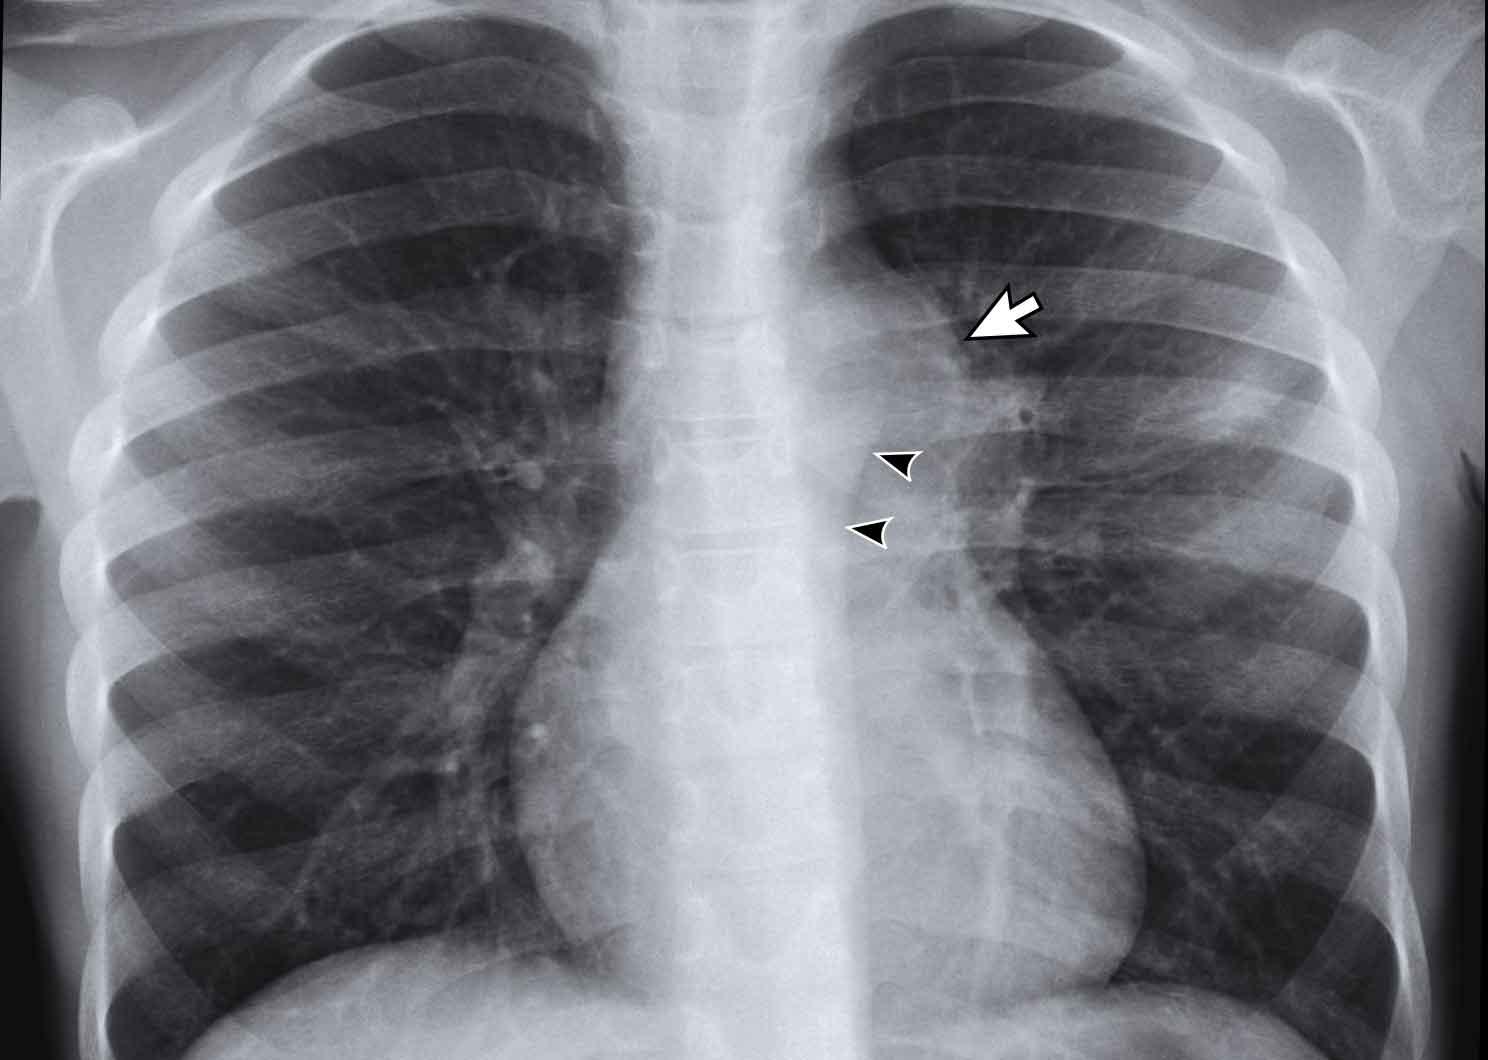

Hình ảnh

Có đường viền kép ở bên trái do hạch bạch huyết to (mũi tên) và động mạch chủ (đầu mũi tên).

Tiếp tục xem CT…

Nhiều hạch bạch huyết trung thất to ở một trẻ em mắc lao hoạt động.

Ở trẻ dưới 2 tuổi, đôi khi thấy xẹp phổi thùy hoặc phân thùy, điển hình liên quan đến phân thùy trước của thùy trên hoặc phân thùy giữa của thùy giữa, thường là kết quả của hạch to lân cận và hiệu ứng chèn ép.